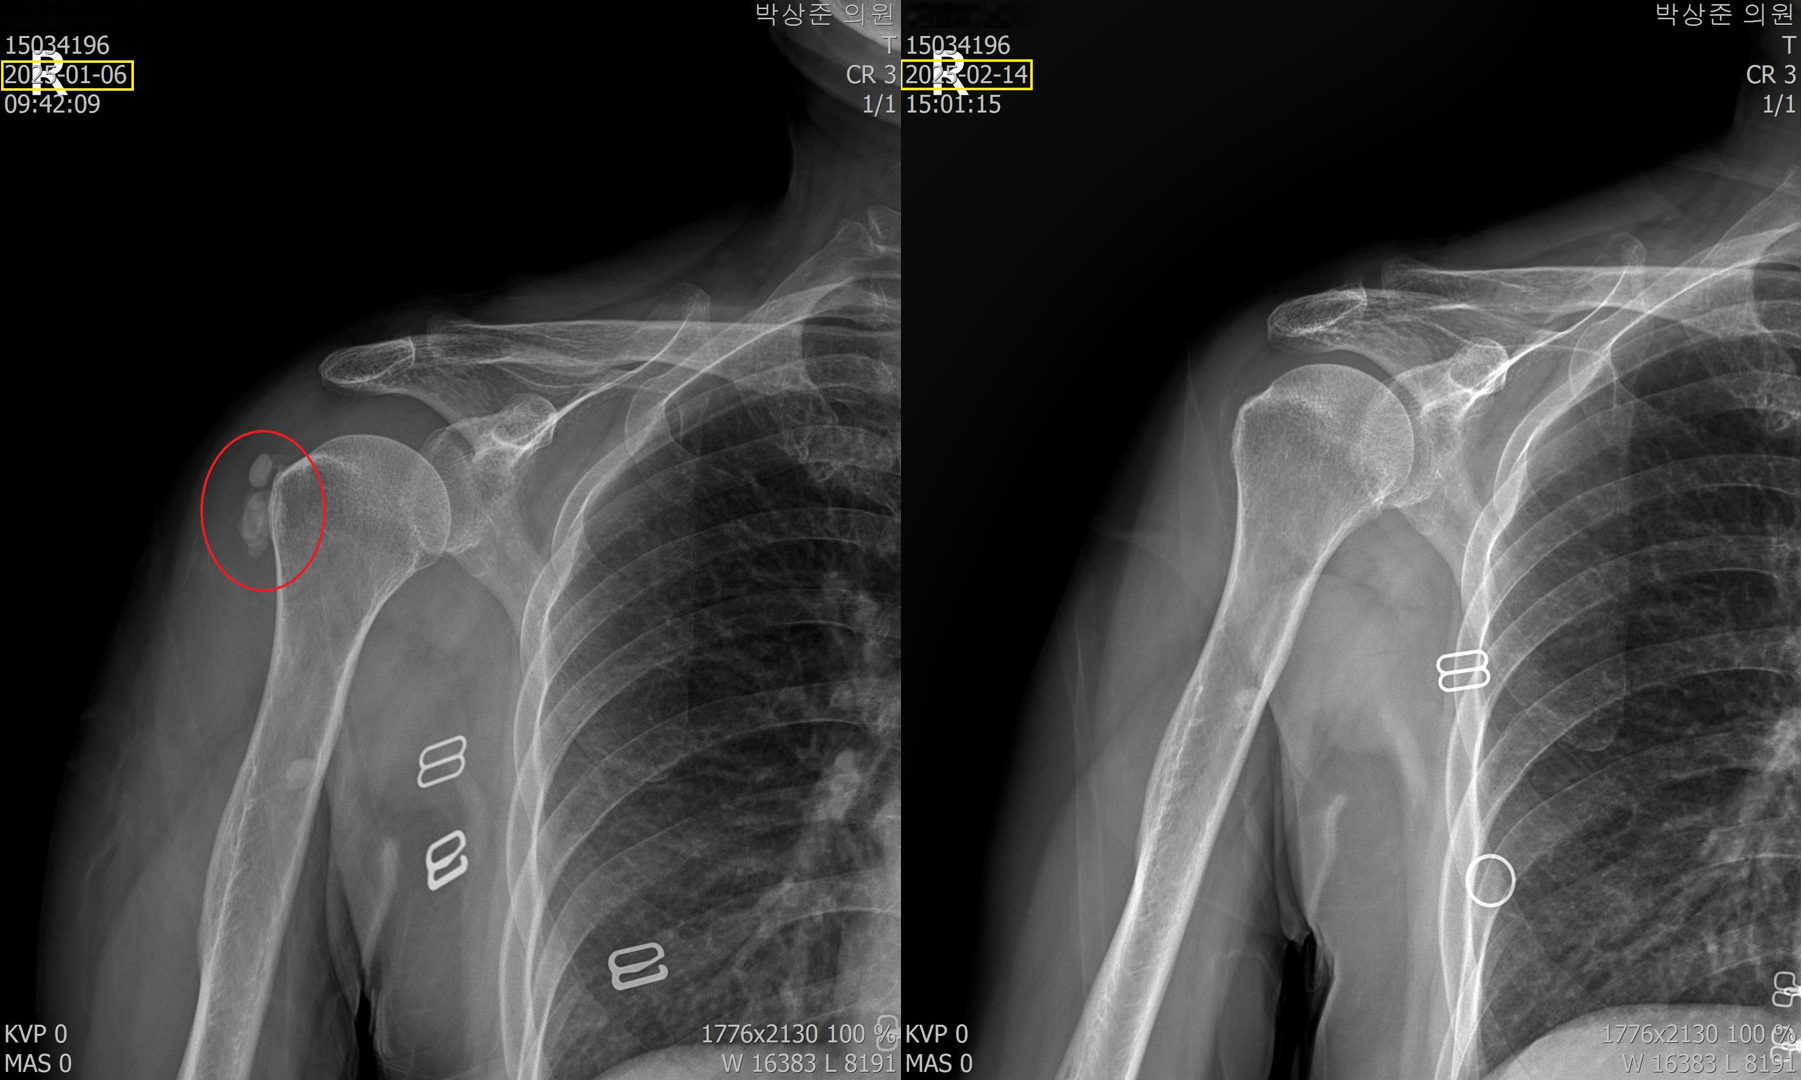

(2) 갑자기 급작스런 어깨 통증으로 방문한 환자

이분은 극심한 통증으로 아침 진료 시작시간 30분전부터 와서 기다리고 있는 분입니다. 내원 3일전부터 약간씩 아프다 내원 전날 밤에 통증이 극심해져서 밤새 잠도 못자고 병원에 오셨습니다. 통증이 워낙 심해서 옷을 입고 벗는것도 스스로 불가능했고 초음파검사기를 가져다 대는것도 아파하는 정도였습니다.

초음파 검사에서 보면 어깨에 아주 커다란 석회가 있고 주변으로 염증이 심한 상태였습니다.

처음에는 염증을 가라앉히는 주사, 먹는약, 물리치료로 통증을 가라앉히고 그 다음부터 5회의 석회흡입술과 체외충격파 치료를 했습니다.

위의 비포 & 애프터 사진을 보면 알 수 있지만 5회의 석회 흡입술과 체외충격파 치료로 아주 커다란 석회가 드라마틱하게 사라진걸 볼 수 있습니다. 이 환자분의 경우 염증 주사를 맞고 이틀만에 통증은 거의다 사라졌고 커다란 석회마저 완전히 제거되어 치료 만족도가 매우 높은 분이었습니다.